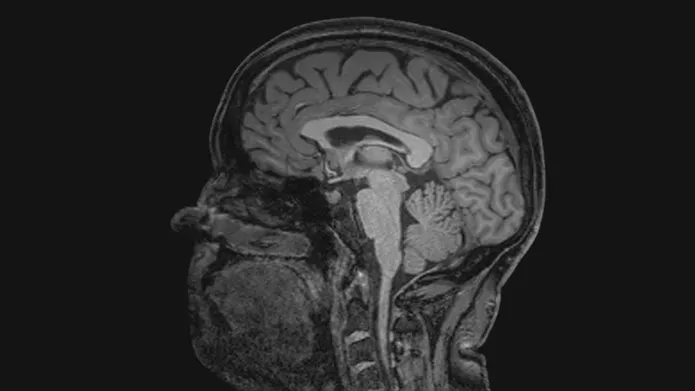

The team of 20, from the Universities of Edinburgh and Dundee, has approval to use a unique, large data set made up of CT and MRI brain scans from patients in Scotland from 2008 to 2018, representing 1.6 million images.

The team will then use artificial intelligence and machine learning to analyse the image data alongside linked health records such as demographics and treatment history, without patients being identifiable, to find patterns that could indicate a person’s risk of developing dementia.

The ultimate aim is to build a digital healthcare tool that radiologists can use when scanning for other conditions to determine a person’s dementia risk, and to diagnose early stages of related diseases, such as Alzheimer’s.